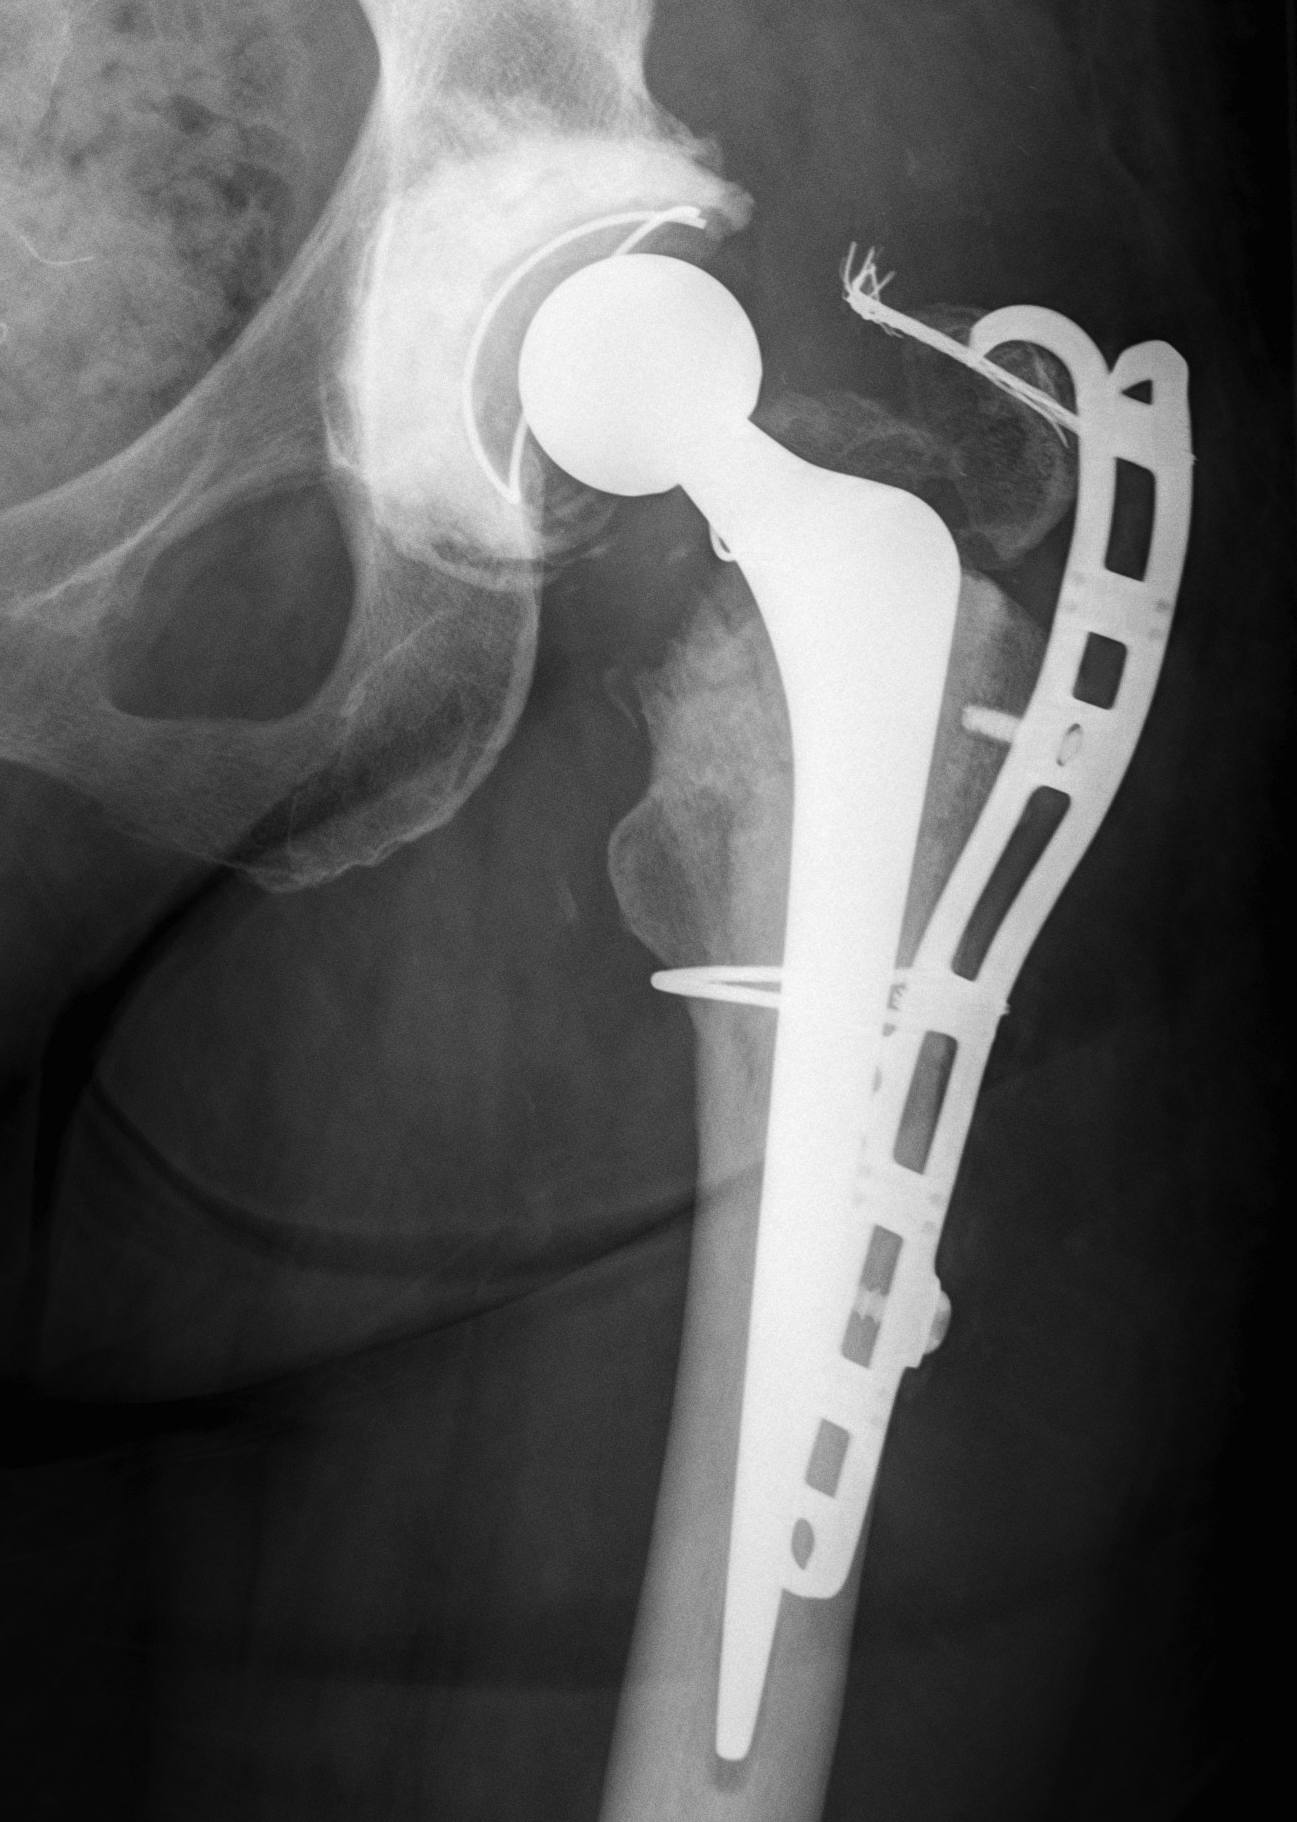

Revision uncemented arthroplasty with Zimmer cable plate